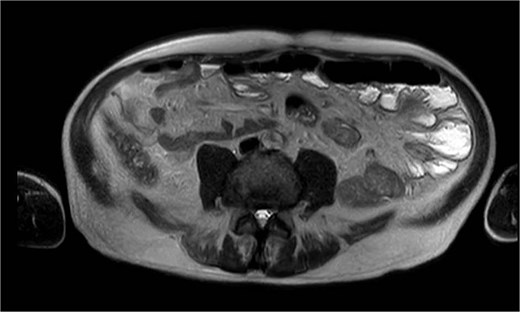

A performed CT scan showed a suspicious process in the left hemiabdomen with the involvement of the small bowel and its mesentery (Fig. 7), as well as enlarged lymph nodes. Therefore a radiological suspicion of malignancy was postulated. Adding to that a mechanical small bowel obstruction was seen in the CT scan due to the described mass.

An antibiotic therapy with piperacillin/tazobactam was empirically initiated as well as a conservative therapy of small bowel obstruction with oral intake of Telebrix®. We also scheduled further investigations ruling out a malignancy. The performed magnetic resonance imaging (MRI) of the abdomen then showed a jejunal diverticulitis (Fig. 8). During the hospital stay we observed a significant decrease of the inflammatory markers, a return of bowel movement with established stool passing as well as a pain-free patient. The antibiotic therapy was discontinued on the day of dismissal, on day 7.

MRI showing multiple jejunal diverticula on the mesenteric side.